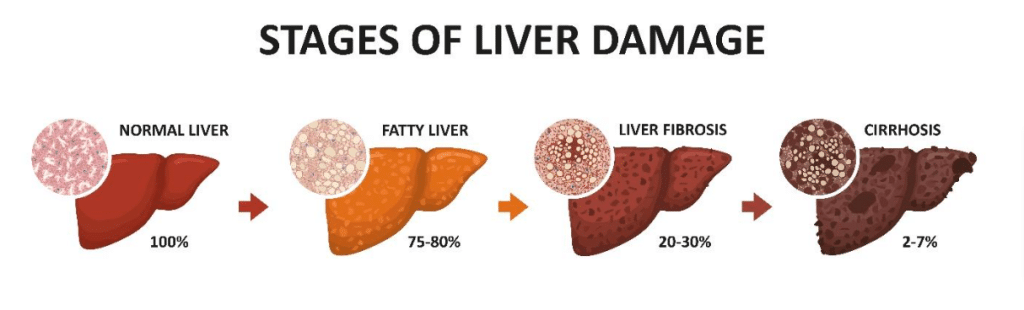

Non-alcoholic fatty liver disease occurs in approximately 40% of Singaporeans and comprises four different stages, these are:

As NAFLD can progress into irreversible complications such as cirrhosis (severe scarring of the liver), regular routine screening is important in the prevention of fatty liver disease.

Once an individual has developed liver cirrhosis, further complications may occur such as a buildup of abdominal fluid (ascites), oesophageal vein swelling and rupture (varices), liver encephalopathy (with change of mental state, confusion, drowsiness), increased risk of liver cancer (hepatocellular carcinoma), and end stage liver failure.

Hence, it is very important to detect and treat NAFLD when it is still in its early, reversible stages. Thankfully, the progression of the condition is generally slow, and most NAFLD patients are stable and can be managed in primary care. Do speak to your doctor to screen for NAFLD.